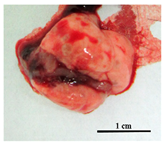

To further define, the virulence of the studied strains, we investigated the tuberculosis process in the C57BL/6 mice models on the 30th day after pathogen injection, when all mice infected by the H37Rv strain were alive, and about 50% of mice infected by the Rostov strain were dead. The pathological processes provided by two M. tuberculosis strains were very different. Animal appearance after infection by the H37Rv strain was characterized by mild depletion and smooth fur, but after infection by the Rostov strain—by extremely emaciated and “ruffled” fur. The differences in survival times were associated with differences in the macroscopic appearance of lungs and liver harvested on the 30th day of infection, when more than 50% of mice infected with the Rostov strain were dead. It was shown that the lungs of mice infected by the Rostov strain were different from those in the H37Rv-infected mice, which appeared in increased lungs volume, intensively hyperemic, and no visible nodules; in turn, the lungs of mice infected by the H37Rv strain were pale pink colored with pale mass inclusions. The similar picture was obtained in the liver: Rostov-infected mice livers were dark brown with multiple nodules and the fatty degeneration was visible, while the livers from H37Rv-infected mice were smooth, dark brown, and normal volume, as shown in Table 2.

Table 2.

Comparative characterization of the mortality, animal appearance and morphological description of internal organs of C57Bl/6 mice infected by the H37Rv and Rostov strains of M. tuberculosis.